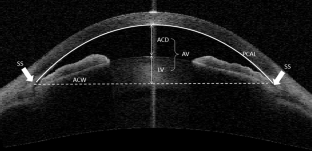

Anterior-segment optical coherence tomography (ASOCT) was performed in primary angle closure suspect (PACS) and primary angle closure glaucoma (PACG) patients. Clustering analysis using age-independent parameters, anterior chamber width (ACW), anterior vault (AV), posterior corneal arc length (PCAL), and iris area was performed. The optimum number of subgroups was determined using Bayesian Information Criterion and subjects were classified into subgroups by Gaussian Mixture Model methods.